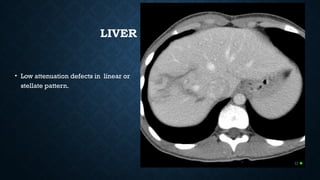

LIVER LACERATION

• Low attenuation defects in linear or

stellate pattern.

LIVER LACERATION • Lowattenuation defects in linear or stellate pattern.